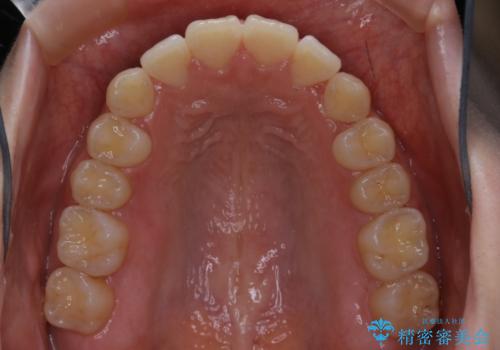

- 前歯の重なりが気になるとご相談にいらした方です。前歯のがたつきは奥歯の噛み合わせのズレが原因となっていたため、インビザラインFULLにて奥歯からしっかり治療していきました。

前歯のがたつきだけを治そうとした場合、噛み合わせは二の次なってしまう事が多く、せっかく綺麗になった歯並びも後戻りしやすくなります。

見た目だけでなく奥歯を移動させて噛み合わせの改善までが行えるのはインビザラインであるからこそです。奥歯の噛み合わせからしっかり機能させることで、長期間にわたって綺麗な歯並びを保ちやすくなります。